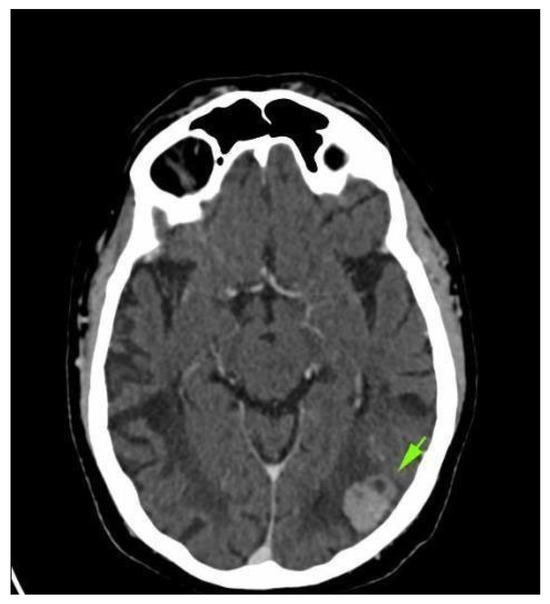

2. Case Presentation